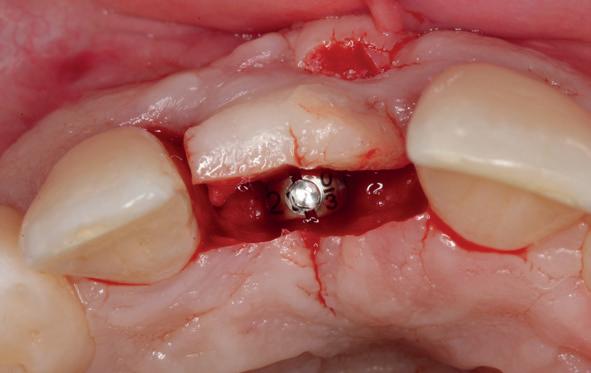

Implantologische behandelingen in het esthetische front vragen meer dan technische vaardigheid alleen. Ze vragen om overzicht, timing, vertrouwen en een team dat als vanzelf samenwerkt onder druk. Juist bij complexe casussen, waarin angst, infectie en hoge esthetische verwachtingen samenkomen, wordt zichtbaar hoe bepalend de rol van de tandartsassistent is.

Deze casus beschrijft een uitgebreide immediate implantaatbehandeling bij een patiënt die door meerdere collega’s werd geweigerd. Niet omdat de mogelijkheden ontbraken, maar omdat de complexiteit vroeg om een perfect afgestemde samenwerking. Het verhaal laat zien hoe de assistent in zo’n traject veel meer is dan een uitvoerende kracht of “mal”, maar een dynamische surgical guide die het proces mede stuurt, bewaakt en mogelijk maakt.De patiënt: wanneer alles samenkomt

Na het klinische onderzoek volgde het röntgenologisch traject. De CBCT liet precies zien wat we al vreesden: een front waarin het bot onregelmatig was, duidelijke radiolucenties rond de pijlers en een infectiegebied dat zich onder vrijwel de gehele brug had verspreid. Tegelijkertijd was er ook potentie. Net voldoende botstructuur om immediate implantaatplaatsing te overwegen, mits alles perfect gepland zou worden.